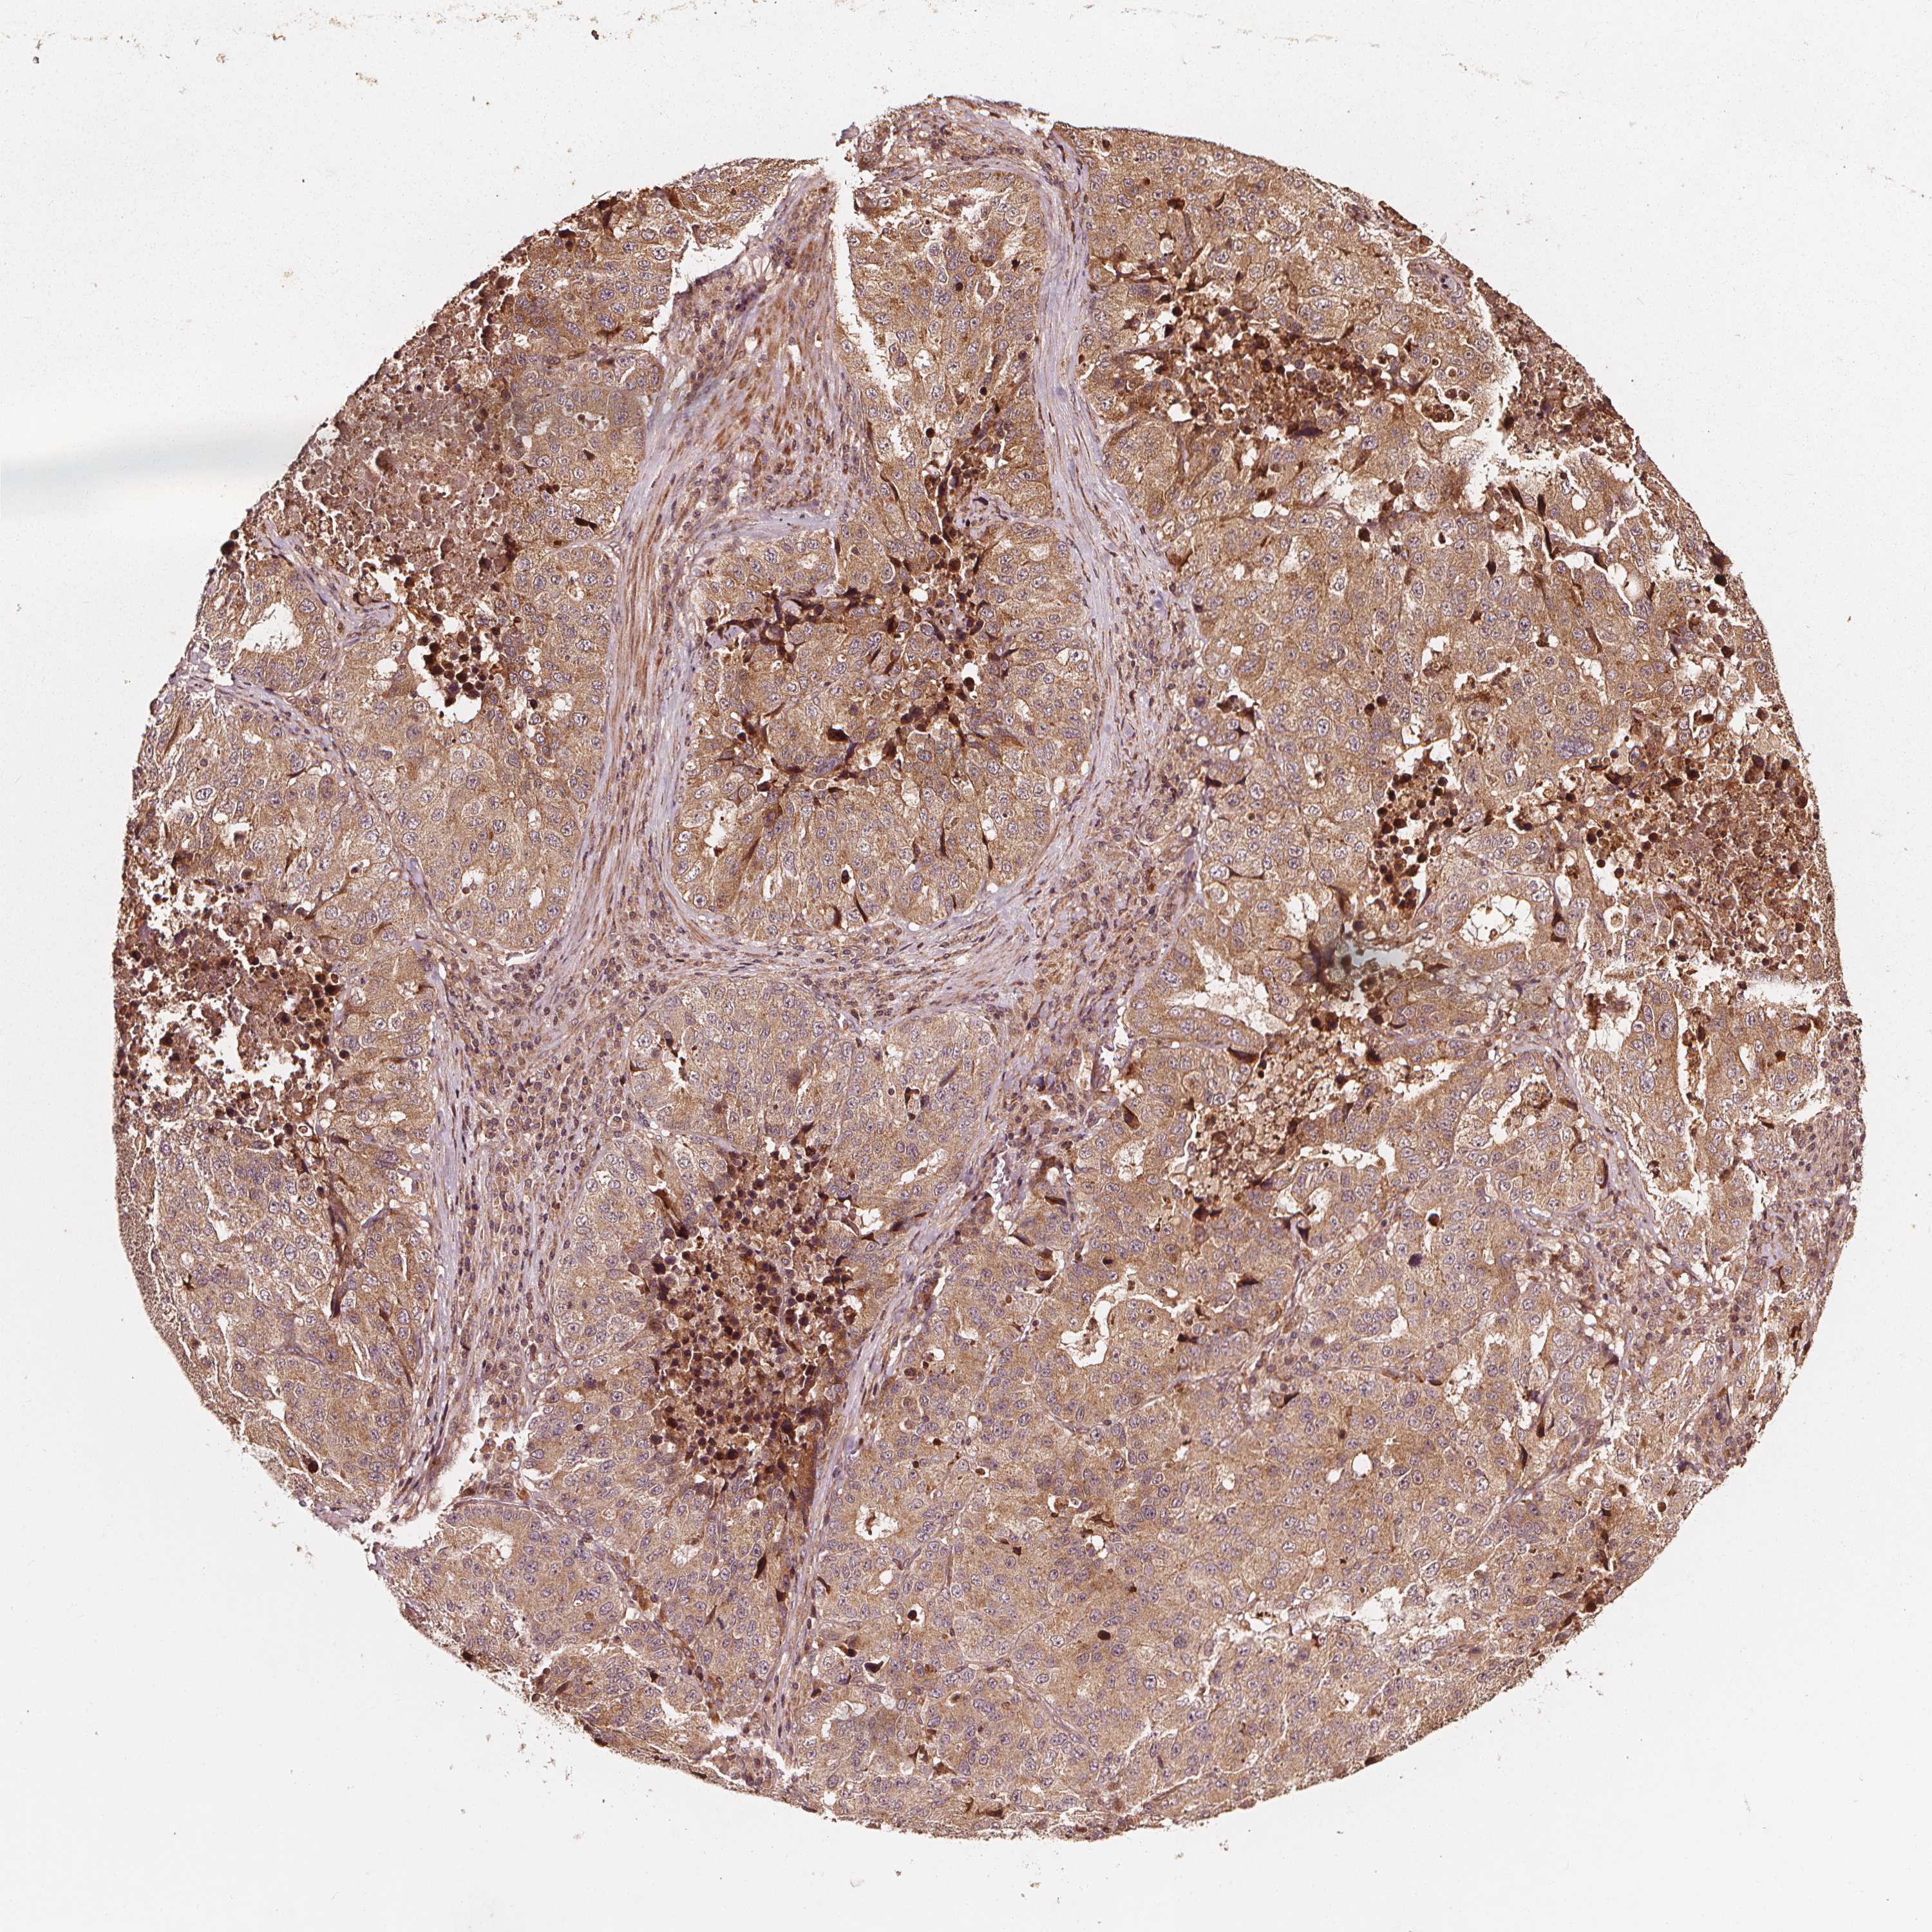

STOMACH CANCER - Protein expressioni

A mouse-over function shows sample information and annotation data. Click on an image to view it in a full screen mode. Samples can be filtered based on level of antibody staining by selecting one or several of the following categories: high, medium, low and not detected. The assay and annotation is described here.

Note that samples used for immunohistochemistry by the Human Protein Atlas do not correspond to samples in the TCGA dataset.

Antibody stainingi

Antibody staining in the annotated cell types in the current human tissue is reported as not detected, low, medium, or high, based on conventional immunohistochemistry profiling in selected tissues. This score is based on the combination of the staining intensity and fraction of stained cells.

Each image is clickable and will lead to virtual microscopy that enables deeper exploration of all samples and also displays staining intensity scores, fraction scores and subcellular localization as well as patient and tissue information for each sample.

Antibody HPA026618

Antibody CAB070132

Staining

High

Medium

Low

Not detected

Intensity

Strong

Moderate

Weak

Negative

Quantity

>75%

75%-25%

<25%

None

Location

Nuclear

Cytoplasmic/membranous

Cytoplasmic/membranous,nuclear

Adenocarcinoma, NOS